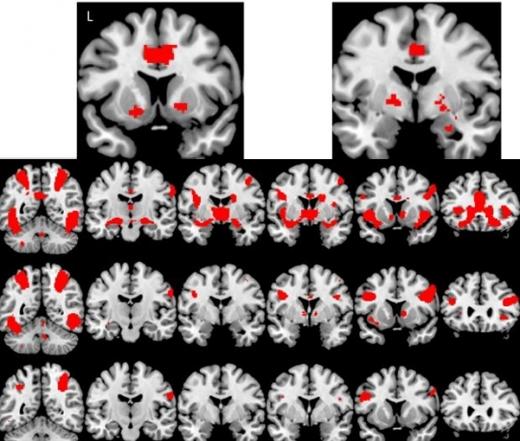

기능적 자기공명영상(fMRI, functional magnetic resonance imaging) 장치를 통해 실험 참가자들의 뇌 혈류 산소 수준(blood oxygen level dependent)을 체크하던 연구진은 특이점을 발견했다. 음란물을 볼 때 강박성행동 장애 환자들의 뇌 활성화 패턴이 정상인 실험자들에 비해 활발하게 변하는 것으로 나타났기 때문이다.

본래 연구진은 음란물 중독자들이 평소 일상에서 성적충동을 참지 못하는 등의 행동패턴을 보이는 것이 마약 중독 증상과 유사하다는 점에서 착안, 해당 실험을 진행했고 결과적으로 음란물 중독과 마약 중독이 뇌에 유사한 형태로 영향을 미친다는 데이터를 얻어냈다.